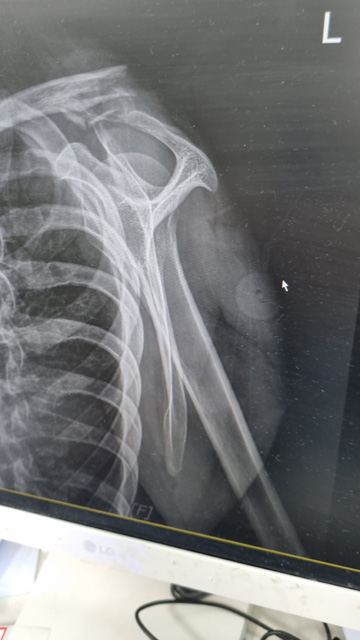

왼쪽 쇄골 골절입니다.

수술을 위해 바로 아빠가 근무하는 병원으로 그 날 밤 옮겨왔고 2023.3.14 화요일 수술을 받았습니다.